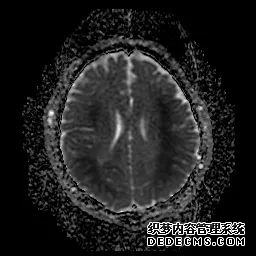

脑MRI显示尾状核、扁豆状核和脑梗头部T2/FLAIR呈双侧对称异常高信号。扩散限制涉及这些区域,其特征是扩散加权DWI(B-1000)上的高强度,ADC图上相应的减弱强度。

印象:通过将这些成像模式与临床和实验室检查结果相结合,就有可能得出低血糖性脑病。

影像影响内囊后肢、大脑皮层(特别是枕叶和岛叶)、海马和基底节区,常是双边对称性的。